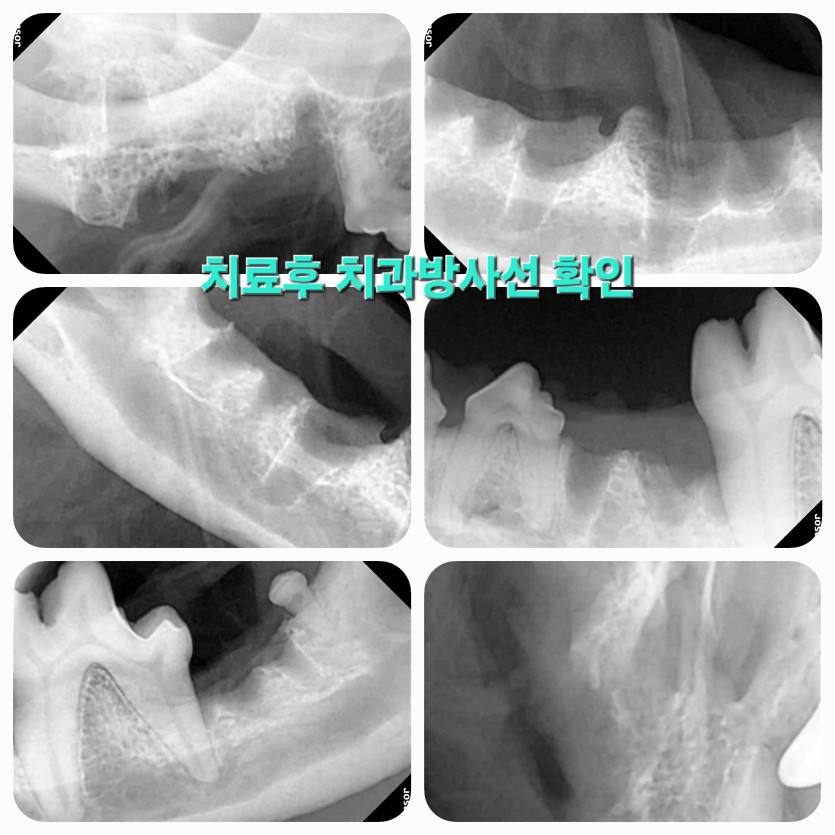

저희 강아지는 매일 양치를 시켜도 치아가 약해 나이가드니 치주염과 이가 썩어서

의사선생님은 초코의 상태를 정확히 진단하시고 아이가 더 이상 아프지 않게 치료해줬어요.